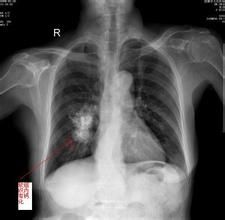

錯構瘤可來自許多組織,常見於肺(由軟骨島、支氣管上皮和腺體等混合,局部增生而形成局限型或瀰漫型錯構瘤)、腎(血管平滑肌脂肪瘤)、乳腺(乳腺小葉脂肪形成的乳腺錯構瘤)和嬰兒肝(間葉性錯構瘤)等。肺錯構瘤

是支氣管的一片組織在胚胎髮育時期倒轉和脫落,被正常肺組織包繞,這一部分組織生長緩慢,也可能在一定時期內不生長,以後逐漸發展形成瘤。大多數在40歲以後發病。腎錯構瘤